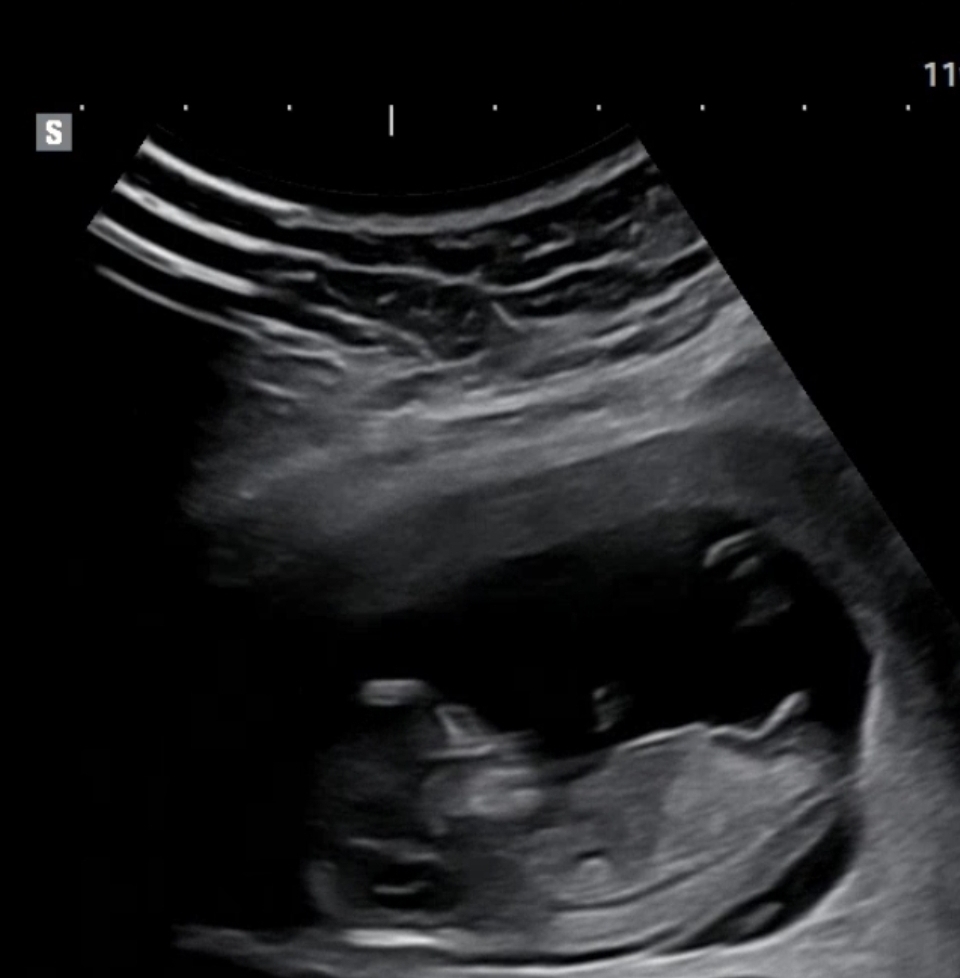

11주6일 각도함께 봐주세요^^!

어제 11주6일차, NT검사&니프티 검사하고왔어요. 쌍둥이라서 시간이 오래걸렸고, 한아이는 제가 생각했을때 딸이 확실한데 두번째아이의 성별이 아무리봐도 헷갈려요 ㅎㅎ 한번 봐주세요♡